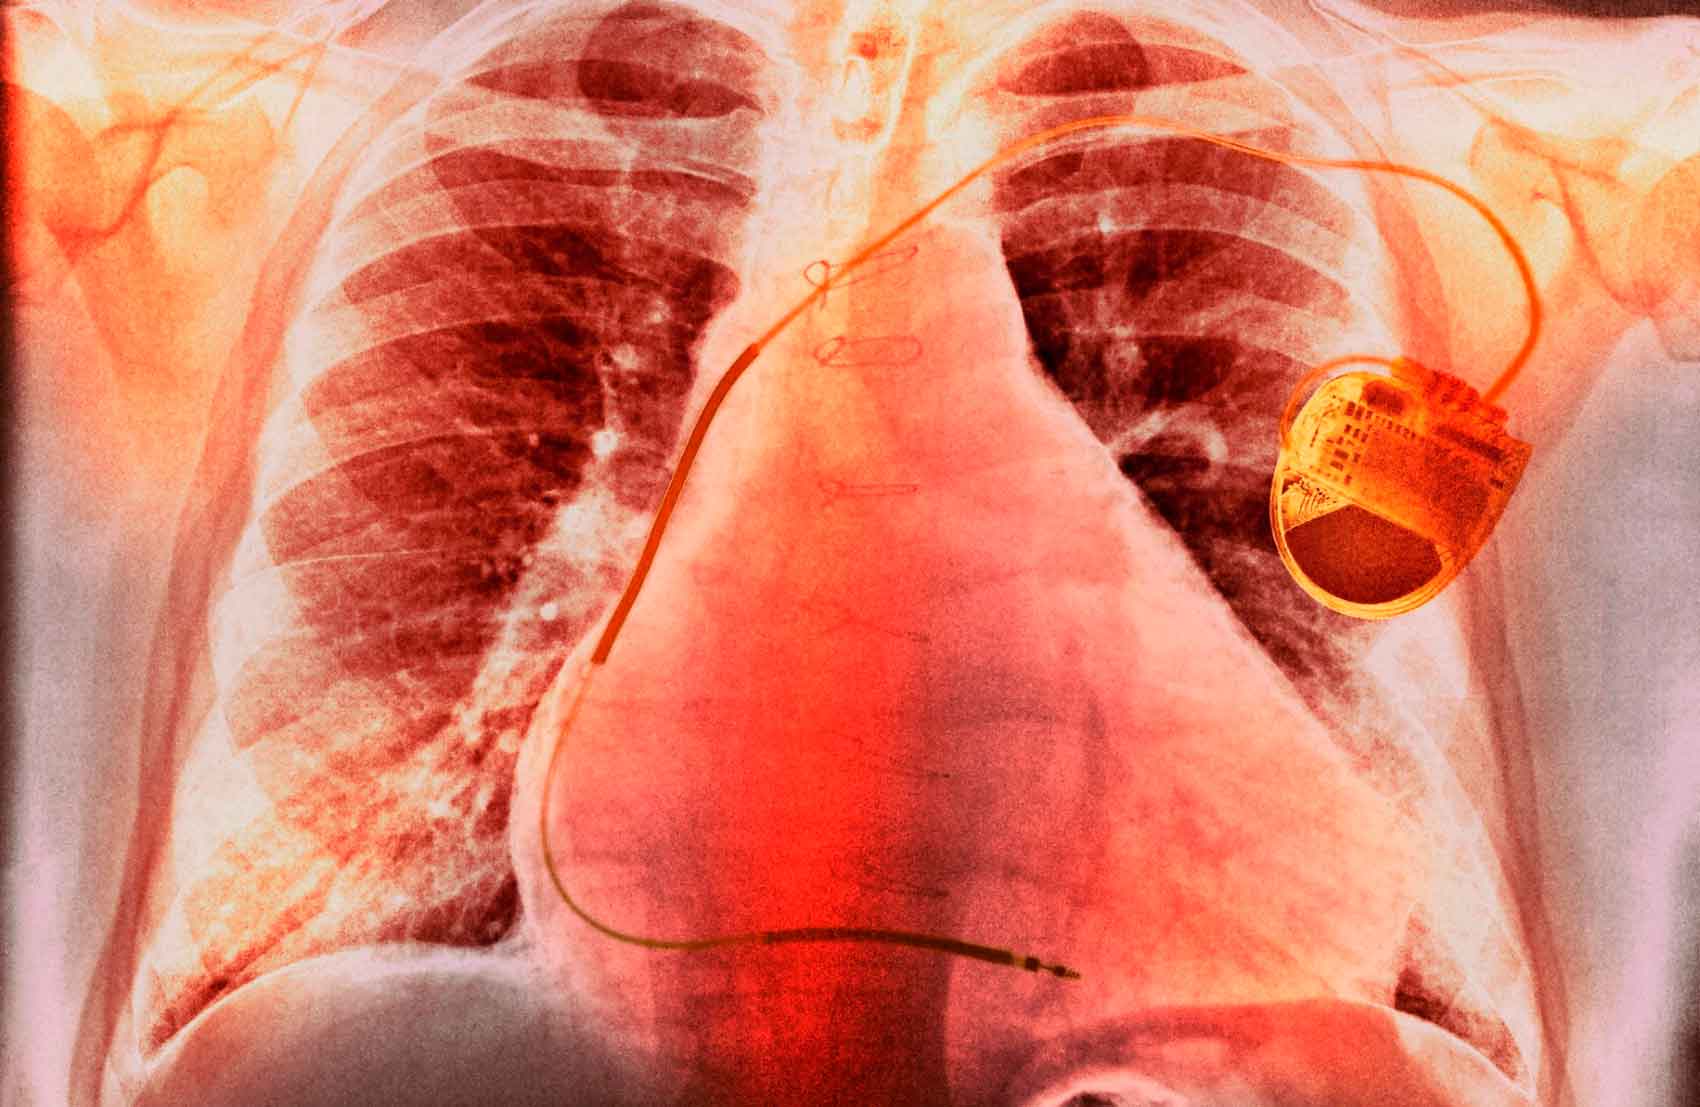

Las arritmias cardiacas son trastornos del ritmo cardíaco que pueden variar desde latidos cardíacos irregulares hasta taquicardias y fibrilación auricular. El síndrome metabólico puede aumentar el riesgo de desarrollar arritmias al alterar la estructura y la función del corazón, lo que puede provocar la aparición de estas anomalías.

Las arritmias más comunes en pacientes con síndrome metabólico incluyen la fibrilación auricular y la taquicardia ventricular. La fibrilación auricular es la arritmia más frecuente y se caracteriza por la contracción irregular y caótica de las aurículas del corazón. La taquicardia ventricular, por su parte, es una arritmia más grave que puede provocar la disminución del flujo sanguíneo al corazón y, en casos graves, puede llevar a un paro cardíaco.